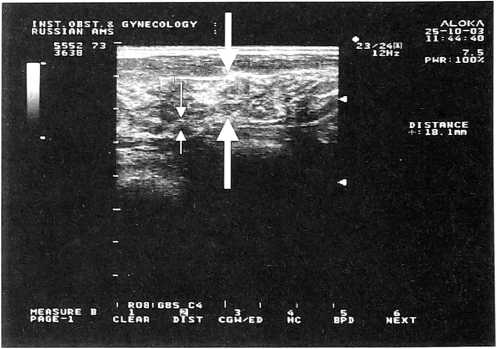

Увеличение толщины паренхимы, средняя эхогенность железистой ткани, отсутствие или слабая выраженность явлений жировой инволюции, расширение протоков характерны для железистого варианта мастопатии (рис. 1); значительное повышение эхогенности железистой ткани с увеличением толщины паренхимы — для фиброзного (рис. 2); наличие множественных кист различного диаметра — для кистозного (рис. 3). Сочетание различных симптомов мастопатии характерно для ее смешанного варианта.

Рис. 3.

Эхограмма молочной железы этой же пациентки (область верхне-наружного квадранта левой молочной железы). Стрелкой указана киста молочной железы (5,4x6,1 мм)